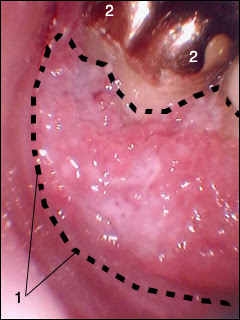

Ο στοματικός καρκίνος εμφανίζεται συνήθως σαν ένα ανώδυνο έλκος (πληγή) στην αρχή, που δεν κλείνει με την πάροδο του χρόνου, αντίθετα μεγαλώνει δημιουργώντας προβλήματα στη μάσηση, την ομιλία ή την κατάποση. Μπορεί να εμφανιστεί και σαν μια λευκή πλάκα ή μια κόκκινη περιοχή.

– λευκοπλακία